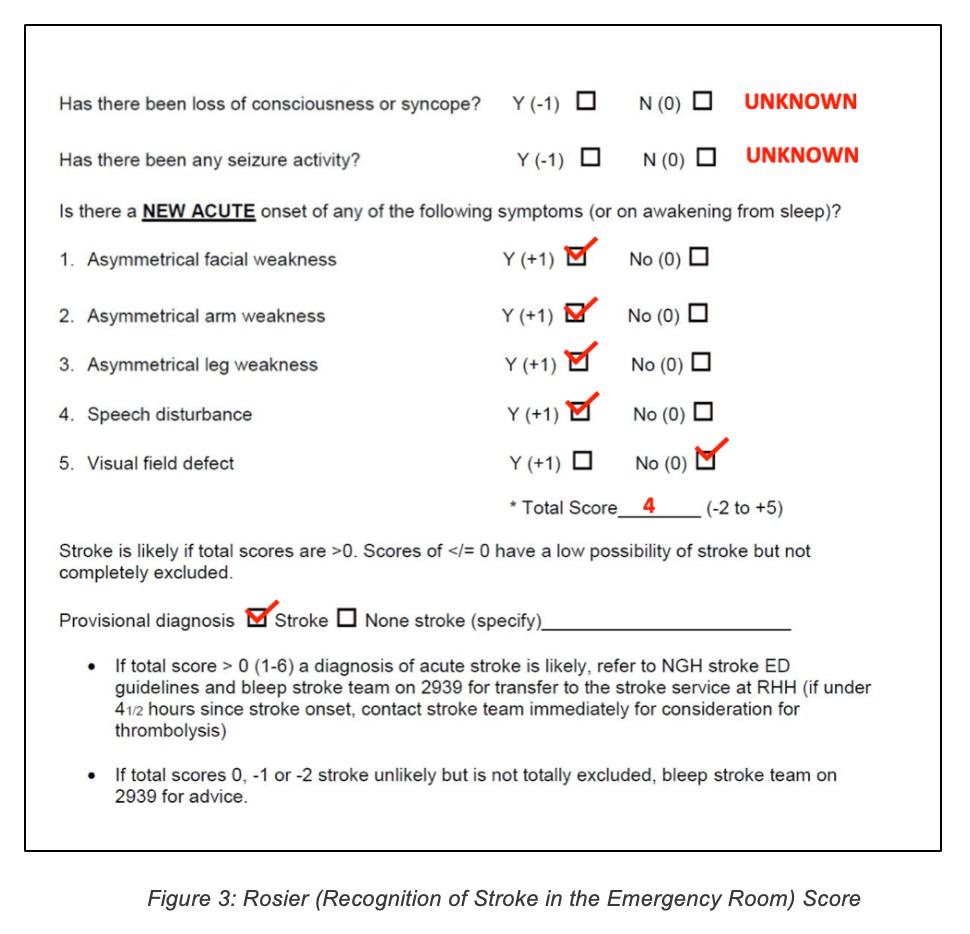

Various stroke screening techniques were used. The results are shown in the following figures:

Investigations ordered: 1. ECG – To identify any predisposing conditions which may have resulted in the stroke e.g.: Atrial fibrillation/flutter, acute myocardial infarction, infective endocarditis etc. In case any are identified, further prophylactic treatment may be indicated. 2. Routine bloods (Complete Blood Count, ESR, CRP, Urea and Electrolytes, Blood Glucose Levels etc) – to rule out underlying conditions such as sepsis, renal disease and diabetes. Inflammatory markers are often raised in ischaemic stroke. In case any are identified, further treatment may be indicated. 3. CT brain – To determine whether the stroke was ischaemic or haemorrhagic in nature, to properly locate the lesion and to rule out any possible differentials such as space occupying lesions. 4. Echocardiogram – To rule out any underlying structural heart disease which may have caused the stroke e.g.: Valvular heart disease, patent foramen ovale, atrial septal aneurysm etc. In case any are identified further prophylactic treatment may be indicated. 5. Carotid doppler ultrasound – To identify any possible stenosis or plaque build-up in the carotid arteries which may predispose to recurrent strokes. If stenosis is greater than 50%, carotid endarterectomy may be indicated. 6. Geriatric review 7. Stroke rehabilitation including outreach to physiotherapy, occupational therapy and